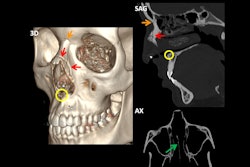

The orbit is delimited by four bony walls: the superior, medial, inferior, and lateral, consisting of a total of eight bones. They are classified according to the involvement of the orbital rim. In the absence of involvement of the orbital rim, they are classified by the displacement of the bony fragments outwards or into the orbit (blowout and blow-in respectively).

“In these cases, it is important to describe the type of fracture, if there is herniation of the orbital fat through the fracture or if there is entrapment of the extraocular muscles, as well as to evaluate possible eye involvement (breakage, hematomas, foreign bodies ...),” noted López, adding that other post-traumatic findings to rule out include carotid-cavernous fistula.

A 20-year-old patient who came to the emergency department following an assault. The CT scan shows a blowout fracture of the orbital floor (circle) with herniation and entrapment of the inferior rectus muscle (arrow).